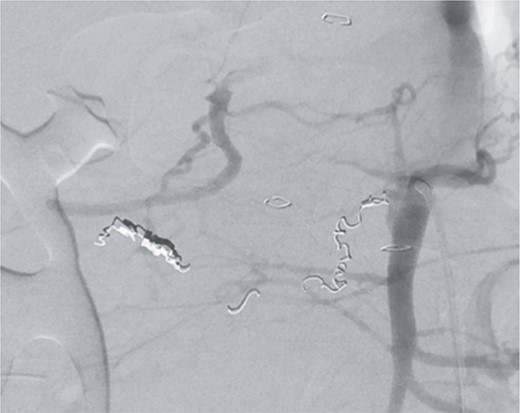

However, on the 16th day following the initial surgery, there was another active bleeding from the pancreaticoduodenal artery, distal to the previously placed coil. This bleeding was also managed interventionally (Figs 4 and 5).

Angiography showing another aneurysm with active bleeding, proximally to the previously coiled site.

Postinterventional angiography, after interventional bleeding control, using coiling.